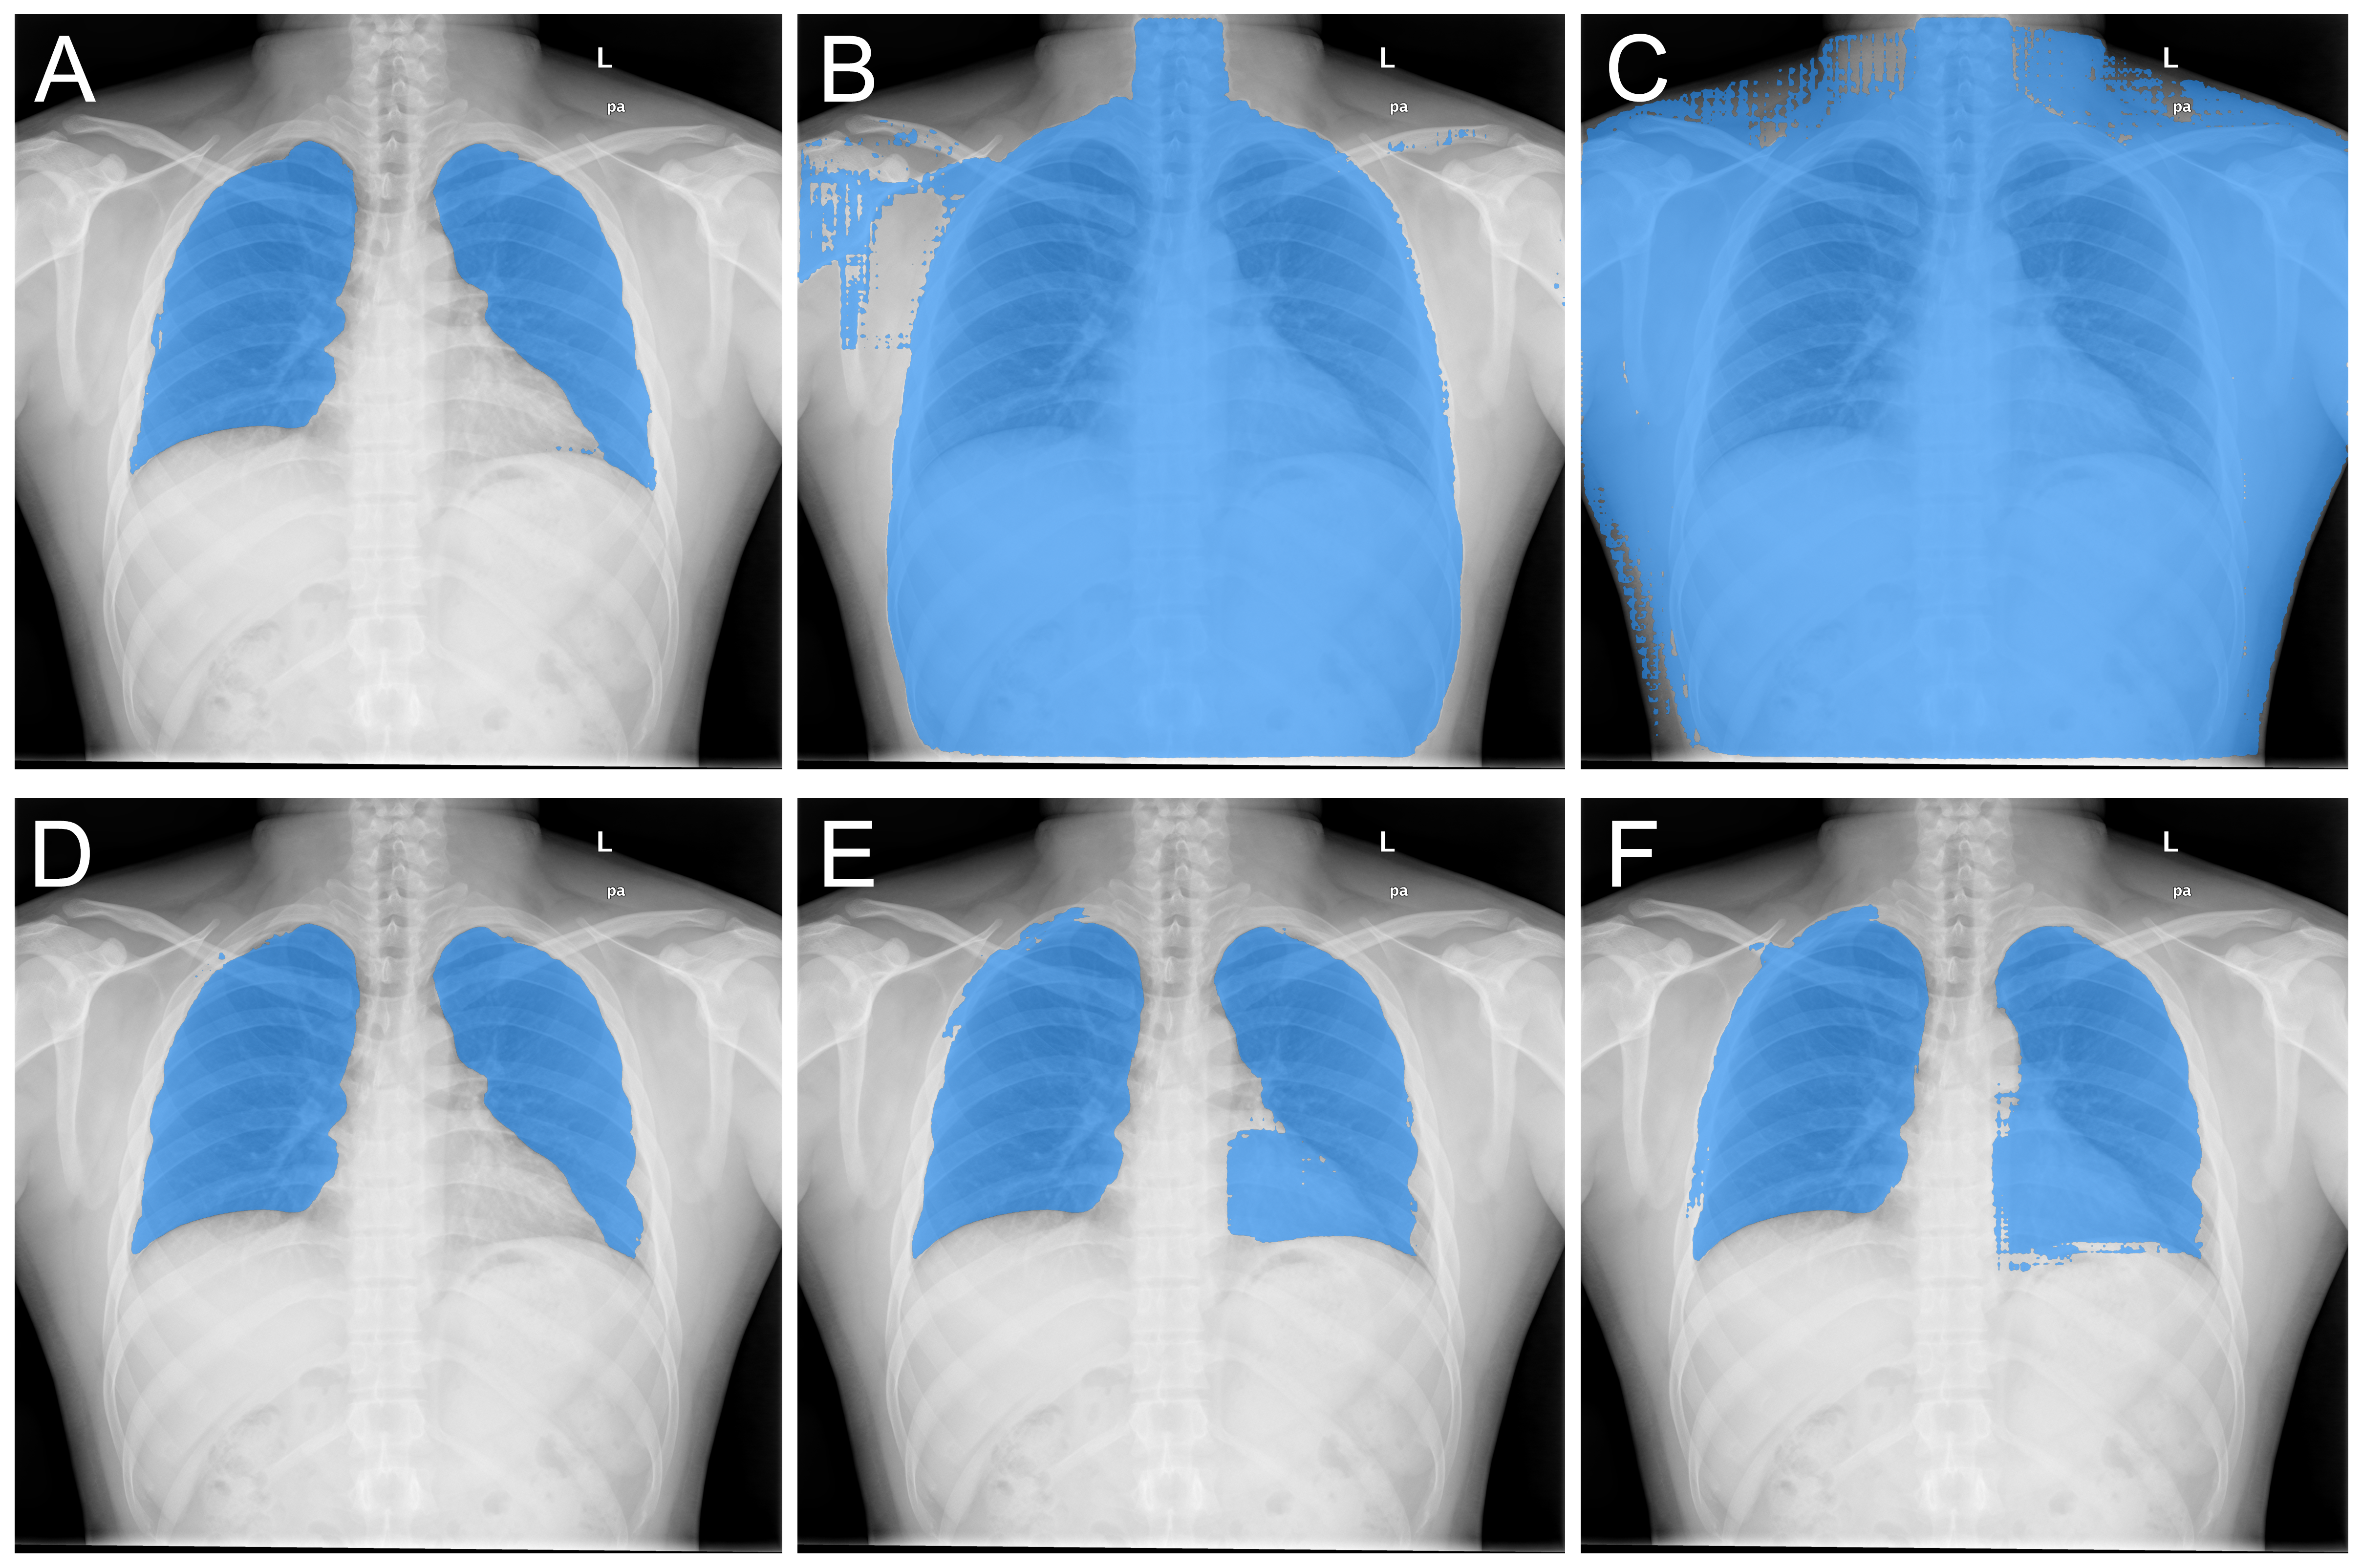

Table 2 shows the DSC of the predictions for ViT-H, the largest SAM model, with results for ViT-B and ViT-L shown in the Supplementary Material. The terms 1st, 2nd, and 3rd correspond to the three predictions generated by SAM, and the table presents the metrics when only one of these predictions is used consistently for all images. Fig 3 showcases an example of these predictions for the Chest X-Ray (CXR) dataset, employing both the RP5 and BBS10 strategies. The RP5 method provides better differentiation between predictions, while the BBS10 approach demonstrates greater uniformity. This observation could potentially be attributed to the bounding box, which simultaneously indicates the target region for segmentation and the areas to be excluded (outside the box).

Refer to caption

Figure 3: Three returning predictions from SAM using RP5 (A, B, C) and BBS10 (D, E, F) input methods for the CXR dataset. A physician may choose the one that best fits the corresponding region to be segmented.